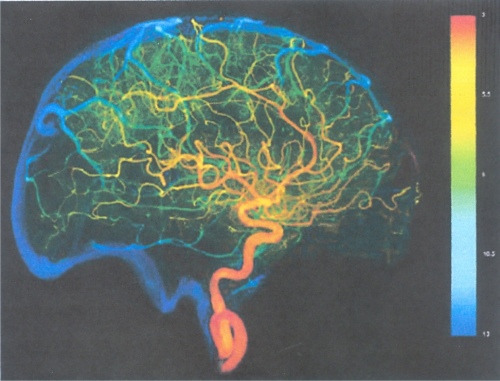

Digital Subtraction Angiography (DSA) awalnya adalah teknik yang dilakukan untuk menggambar pembuluh darah, dengan menyemprotkan zat kontras (iodine) agar bisa dideteksi oleh alat X-ray melalui film. DSA bisa diaplikasikan pada pembuluhjantung, kepala, kaki, perut, hati, dU. Penggunaan iodine dikarenakan eairan tersebut terlihat jelas pada X-ray, serta dapat dengan mudah diserap dan dikeluarkan oleh tubuh.

Pada DSA konvensional, untuk menggambar pembuluh otak, eairan kontras disemprotkan melalui pembuluh leher sebagai pembuluh terdekat. Film yang digunakan pun berlapis-Iapis. Kini dengan teknologi terkini dan sistem digital yang terkomputerisasi, DSA bisa mendeteksi abnormaIitas pada pembuluh darah seeara lebih jelas dan terukur, serta penggunaan eairan kontras seminimal mungkin. Kemajuan paling signifikan dibandingkan sistem konvensional, adalah penggunaan kateter (selang keeil dengan diameter lebih keeil dari 2 mm) melalui pembuluh kaki (femoral). Selain lebih nyaman, prosedur yang dikenal sebagai Trans Femoral Cerebral Angiography (TFCA) ini juga lebih aman bagi pasien, karena pembuluh leher (earotis) memiIiki sensitivitas yang vital bagi lanearnya darah dari dan menuju otak. Jadi dengan tindakan invasif seminimal mungkin, hasil yang dieapai pun lebih baik.